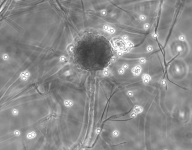

| Species Name: | Rhizopus microsporus var. microsporus |

| Taxonomy: | FUNGI Mucoromycota, Mucoromycetes, Mucorales, Rhizopodaceae |

| Substrate: | sputum, male 61 yr with chronic obstructive pulmonary disease and untreated diabetes | Location: | USA Massachusetts, Worcester (GEO: 42.263,-71.802) |

| Characters: | HUMAN/ ANIMAL PATHOGEN multifocal lung infection following brush clearing - Tsyrkunou AV, Ellison RT 3rd, Akalin A, Wiederhold N, Sutton DA, Lindner J, Fan H, Levitz SM, Zivna I, Med Mycol Case Rep. 8;6:14-7, 2014 (Click for publications citing UAMH 11833) |